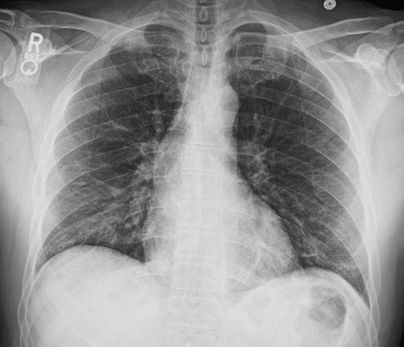

4.3. ЛУЧЕВАЯ ДИАГНОСТИКА COVID-19

Методы лучевой диагностики применяют для выявления COVID-19 пневмоний, их осложнений, дифференциальной диагностики с другими заболеваниями легких, а также для определения степени выраженности и динамики изменений, оценки эффективности проводимой терапии.

К методам лучевой диагностики патологии ОГК пациентов с предполагаемой/установленной COVID-19 пневмонией относят:

- Обзорную рентгенографию легких (РГ),

Стандартная РГ имеет низкую чувствительность в выявлении начальных изменений в первые дни заболевания и не может применяться для ранней диагностики. Информативность РГ повышается с увеличением длительности течения пневмонии. Рентгенография с использованием передвижных (палатных) аппаратов является основным методом лучевой диагностики патологии ОГК в отделениях реанимации и интенсивной терапии (ОРИТ). Применение передвижного (палатного) аппарата оправдано и для проведения обычных РГ исследований в рентгеновском кабинете. В стационарных условиях относительным преимуществом РГ в сравнении с КТ являются большая пропускная способность. Метод позволяет уверенно выявлять тяжелые формы пневмоний и отек легких различной природы, которые требуют госпитализации, в том числе направления в ОРИТ.

Вместе с тем, комплексная оценка анамнестических, клинических и рентгенологических данных позволяет определить клинически подтвержденный случай COVID-19, маршрутизировать пациента и начать противовирусную терапию.

5. Рекомендовано проведение лучевого исследования пациентам при среднетяжелом, тяжелом и крайне тяжелом течении ОРИ с целью медицинской сортировки, оценки характера изменений в грудной полости и определения прогноза заболевания:

- выполнение КТ легких без внутривенного контрастирования в стационарных условиях или в амбулаторных - при показаниях к госпитализации;

- выполнение РГ легких в двух проекциях, если проведение КТ в данной медицинской организации/клинической ситуации невозможно.